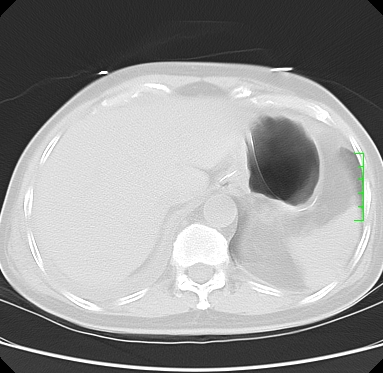

icu病人,几天都没明确诊断。m,76y,咳嗽、咳痰1周,伴气促,右胸痛入院,pe:t38.3c p135 r25 bp135/85。双肺可闻及大量湿罗音,心、腹未见明显异常。诊断:1心衰?2肺部感染?3冠心病?

9号平片

11号ct